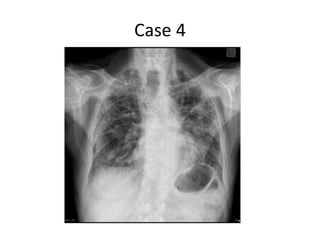

Case 4

Interstitial Lung Disease – A quick

guide

• Umbrella term.

• Consider:

• 1) Idiopathic interstitial pneumonias of which

usual interstitial pneumonia is commonest type

(also known as idiopathic pulmonary fibrosis)

• 2) Interstitial lung disease of known cause –

connective tissue disease, drug related, dusts

which may be organic or inorganic.

• 3) Granulomatous interstitial lung disease –

sarcoidosis.

Interstitial Lung Disease– A quick guide • Umbrella term. • Consider: • 1) Idiopathic interstitial pneumonias of which usual interstitial pneumonia is commonest type (also known as idiopathic pulmonary fibrosis) • 2) Interstitial lung disease of known cause – connective tissue disease, drug related, dusts which may be organic or inorganic. • 3) Granulomatous interstitial lung disease – sarcoidosis.